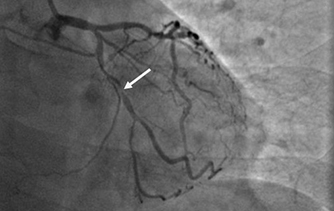

近日,河北醫科大學附屬燕達醫院心血管內三科成功完成一例非常特殊的手術——冠心病三支病變微創介入完全血運重建術。患者李先生冠心病病變極其嚴重,全部三支主干動脈均重度狹窄,各處求診均被告知無法微創介入手術,只能開胸搭橋。拒絕開胸的李先生慕燕達醫院心血管內三科北京安貞醫院專家團隊之名,就診于燕達醫院,由翟光耀主任為其行 “一站式”手術,一 次 性完成三支動脈的修復!手術非常成功,李先生術后恢復良好,滿意出院。 震驚 患者三支血管均90-99%狹窄 ..